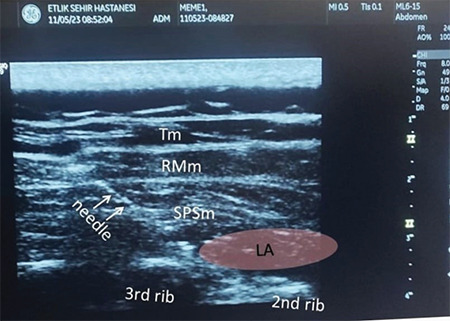

The serratus posterior superior intercostal plane (SPSIP) block is a novel technique recently described for thoracic analgesia. This study presents two cases using this technique for postoperative pain after mastectomy with axillary lymph node dissection. The SPSIP block was administered to the patients in the preoperative period as part of multimodal analgesia, and postoperative pain was monitored using the numeric rating scale (NRS). In both patients, the NRS pain scores were below 3/10. SPSIP provided adequate postoperative analgesia in these cases without the need for any opioid agents. Thus, an SPSIP block can be a valuable treatment option for postoperative pain after breast surgery.